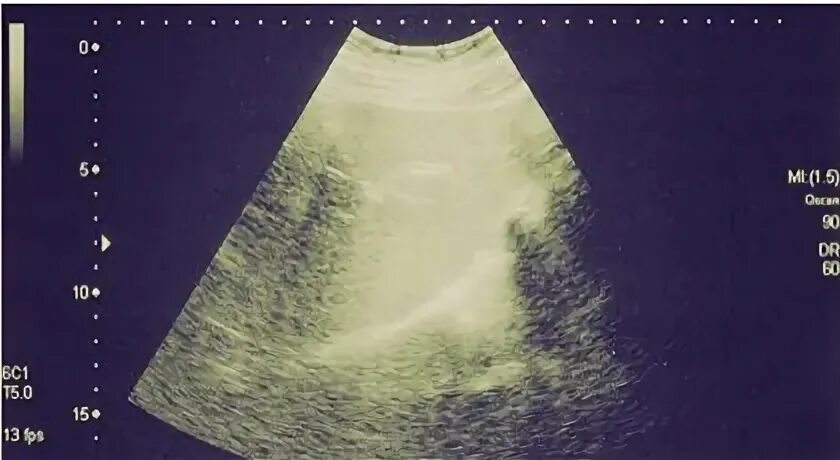

Узи желчного пузыря подготовка к процедуре